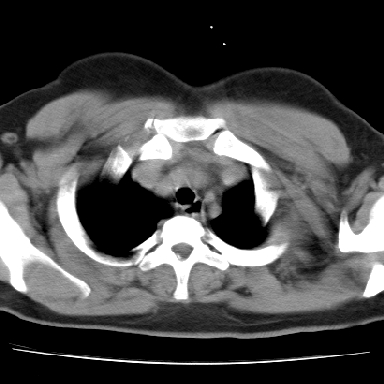

支持。另外,双侧腋下似见增大淋巴结影,有侧乳腺4、5点处皮下高密度结节影是什么?食管中下段有没有问题?病人比较年轻,因此诊断恶性肿瘤要慎重,多结合临床和其他检查,多考虑一些,也可短期抗炎治疗后复查。

左下肺有空洞,壁厚薄不均,壁结节,两肺多发小结节影,腋窝下可疑淋巴结肿大,综上所述考虑周围性肺癌并两肺转移可能性大,建议穿刺活检。

右肺多发小结节影,边界清楚,符合转移瘤的特点;2、左下肺偏心性空洞影,右侧乳腺内高密度影,需要查体除外右侧乳腺肿瘤;3、腋窝淋巴结肿大,考虑转移。